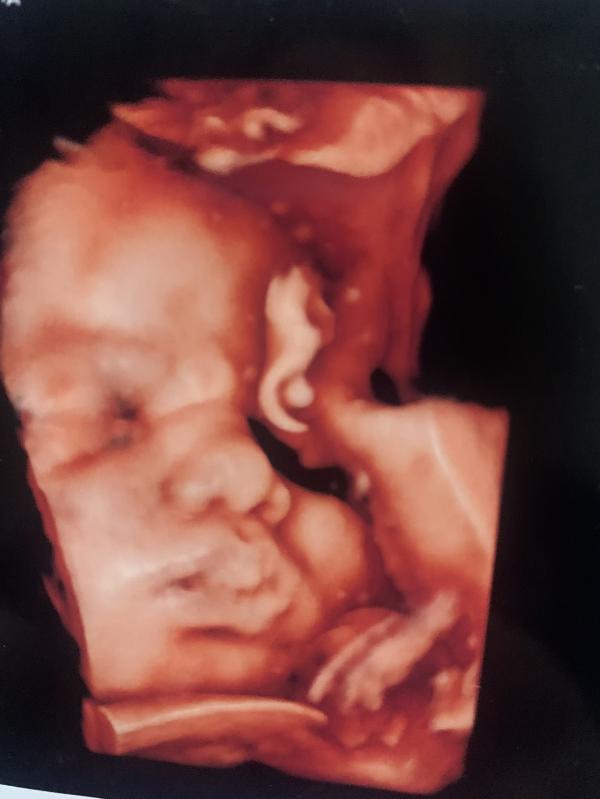

Сегодня сходила во второй роддом ,такие очереди были на УЗИ ,в итоге я записалась к Зареме Касумовне в здоровье ,по совету одной девушки с мамлайфа 💗такая душка ,все показала ,тщательно осмотрела ,и фотки чедкие сделала за 2900р.Мой малыш даже не думает выходить шейка за три недели только 3мм уменьшилась 🙊было 23 а щас 20,зато убрал пуповину с шеи это порадовало ,вес 3900.всем спасибо!всем пока!